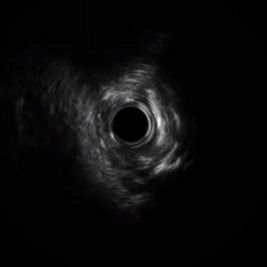

Barrido inicial de IVUS

Barrido inicial del IVUS

• Se pasó una guía coronaria de alto rendimiento a través de la lesión de forma satisfactoria. Se intentó la predilatación con un balón semicompliante RX de 2,0 x 12 mm, pero no tuvo éxito porque no pudo atravesar la lesión.

• La predilatación fue satisfactoria con un balón APEX™ Push de 1,5 x 12 mm; el angiograma posterior mostró la restauración del flujo de TIMI-3.

• Posteriormente, se realizó una predilatación adicional con un balón de 2,5 x 12 mm NC QUANTUM APEX™ MR a alta presión. Hubo una clara expansión del balón bajo fluoroscopia.

• La ecografía intravascular mostró un vaso muy estrechado con una sustancial placa fibro-cálcica. Dados estos hallazgos, se tomó la decisión de continuar con ROTABLATOR.